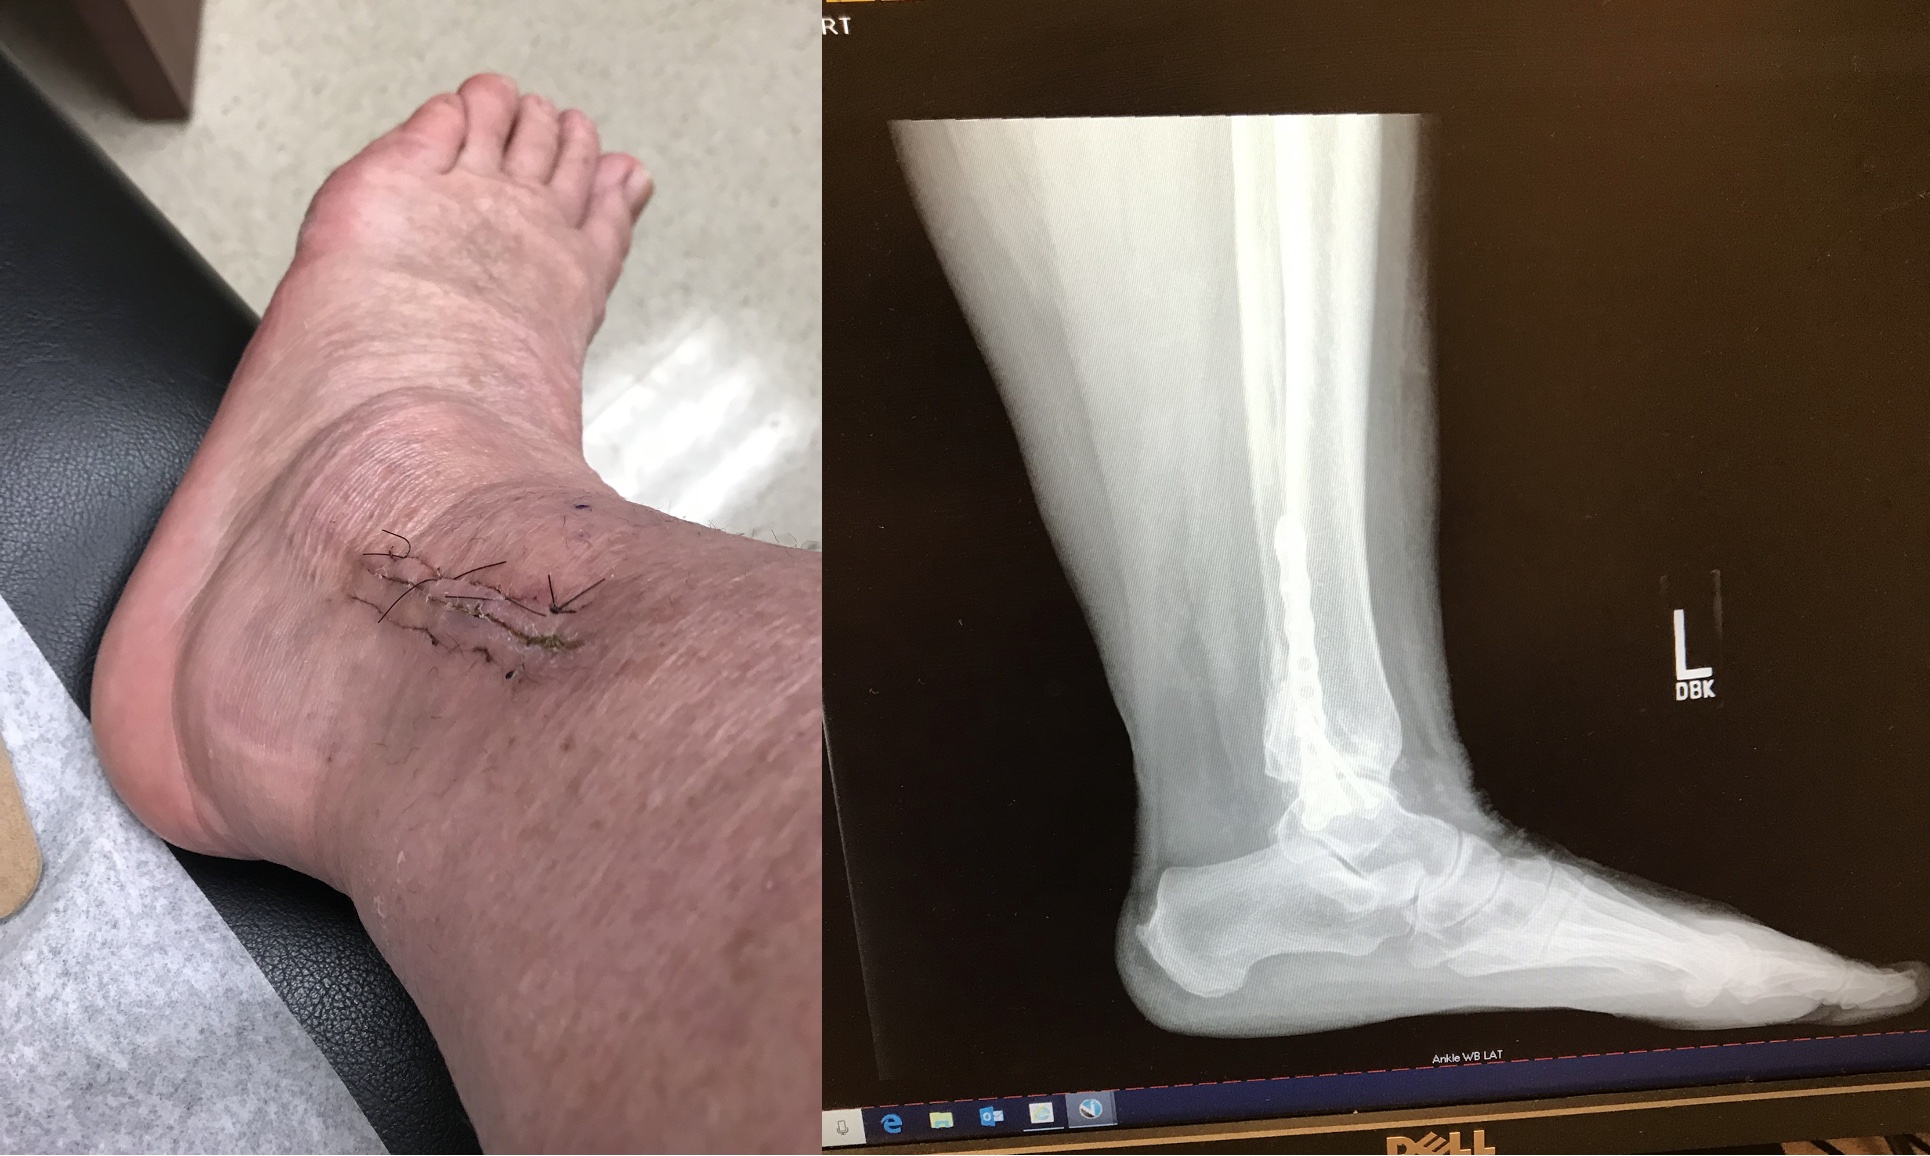

I have seen Jimmy a few times in the last 20 years after seeing other physical therapist. There is no comparison. Not only does he fix the problem but helps you to understand why you are having the pain and correct the behaviors causing the pain. After an accident that required 2 surgeries , he had me up in time for 10 miles of walking at Disney and skiing the next season. He truly cares about his patients!